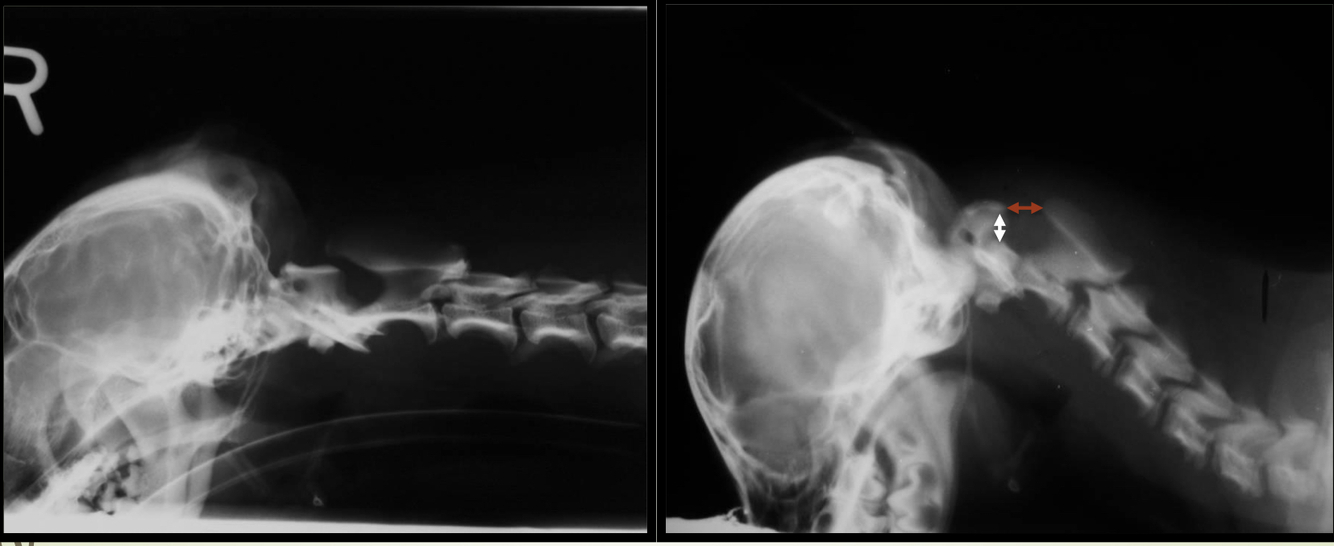

Subluxación atlantoaxial

A

• Inestabilidad de la articulación por hipo/aplacia o fractura del diente del axis

• Excesiva flexión de la art. atlantoaxial

• Compresión del canal medular

SC :

* Normalmente < 1 año (!hasta 9 año)

* Lesion en c1-c5 :

1° Dolor → Ataxia → Tetraparesis → Tetraplejia y muerte

DX : rx simple !!!!OJO, flexionar un poquito

TTO :

* Quirurgico : 80% exito - 15% mortalidad perioperatoria

* Inmobilizacion : si solo hay dolor, sin deficit neuro, 55% exito